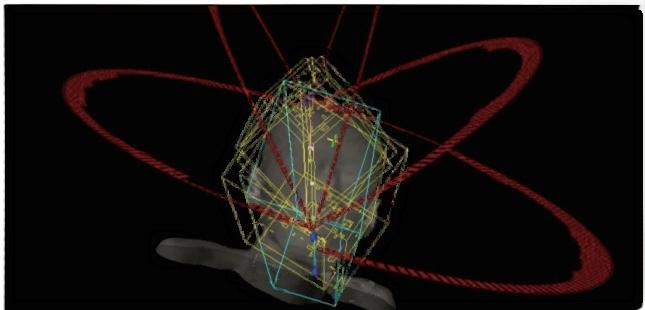

HyperArc technology

HyperArc is a non-coplanar stereotactic radiosurgery technology developed specifically for intracranial tumors. It has the characteristics of high precision, high efficiency and high automation. It has sub-millimeter accuracy and can complete the fixed-point radiosurgery treatment of several to dozens of brain metastases at the same time within 10 minutes, bringing better experience to patients with multiple brain me-tastases.

VMAT

HyperArc